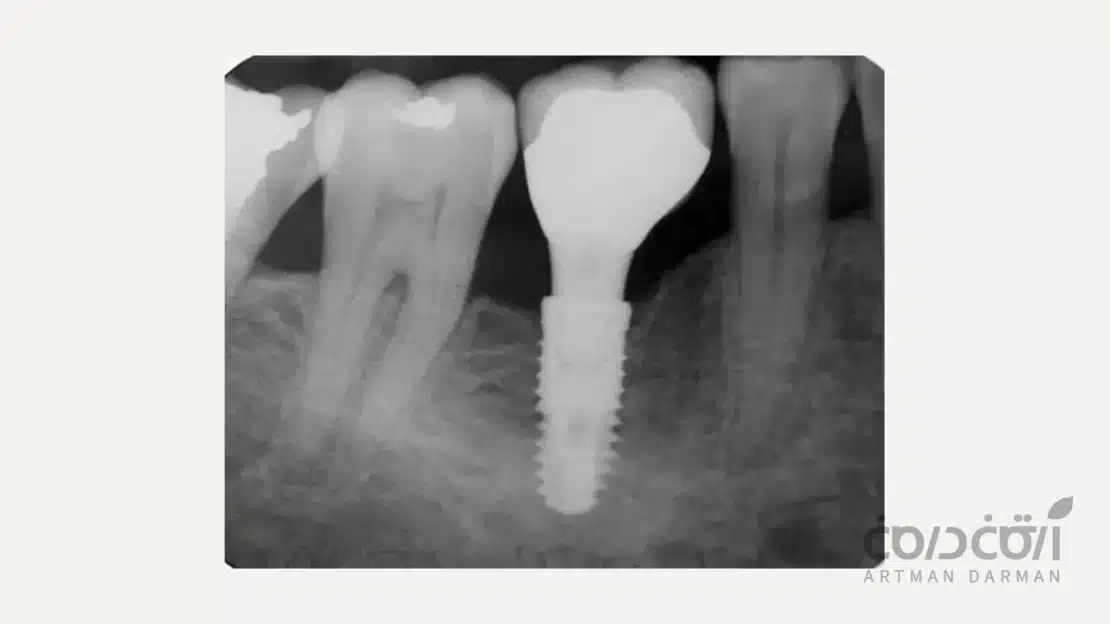

پایه ایمپلنت یا فیکسچر

فونداسیون کل سیستم، همین پایه پیچی شکل است که طی یک فرآیند جراحی در استخوان فک قرار می گیرد. جنس آن معمولاً از تیتانیوم گرید پزشکی است که با بدن سازگاری کامل دارد و هیچ واکنش آلرژیکی ایجاد نمی کند.

این قطعه به عنوان ریشه مصنوعی دندان عمل می کند و موفقیت بلندمدت درمان به جوش خوردن کامل آن به استخوان بستگی دارد. طراحی رزوه ها و پردازش سطح این قطعه، حاصل دهه ها تحقیق و توسعه علمی است.

زمانی که پایه ایمپلنت دندان از جنس تیتانیوم در استخوان فک قرار می گیرد، بدن آن را به عنوان یک جسم خارجی متخاصم شناسایی نمی کند. در عوض، سلول های استخوان ساز بدن (استئوبلاست ها) سطح ایمپلنت را به عنوان یک بستر مناسب برای رشد شناسایی کرده و به آن مهاجرت می کنند.

این سلول ها شروع به ساختن استخوان جدید (به طور مستقیم روی سطح ایمپلنت) می کنند. در طی یک دوره چند ماهه، استخوان به تدریج در تمام خلل و فرج میکروسکوپی سطح ایمپلنت رشد کرده و یک اتصال زنده، مستقیم و فوق العاده محکم بین استخوان و ایمپلنت ایجاد می کند. این فرآیند، ایمپلنت دندان را به معنای واقعی کلمه به بخشی از آناتومی فک شما تبدیل می کند.